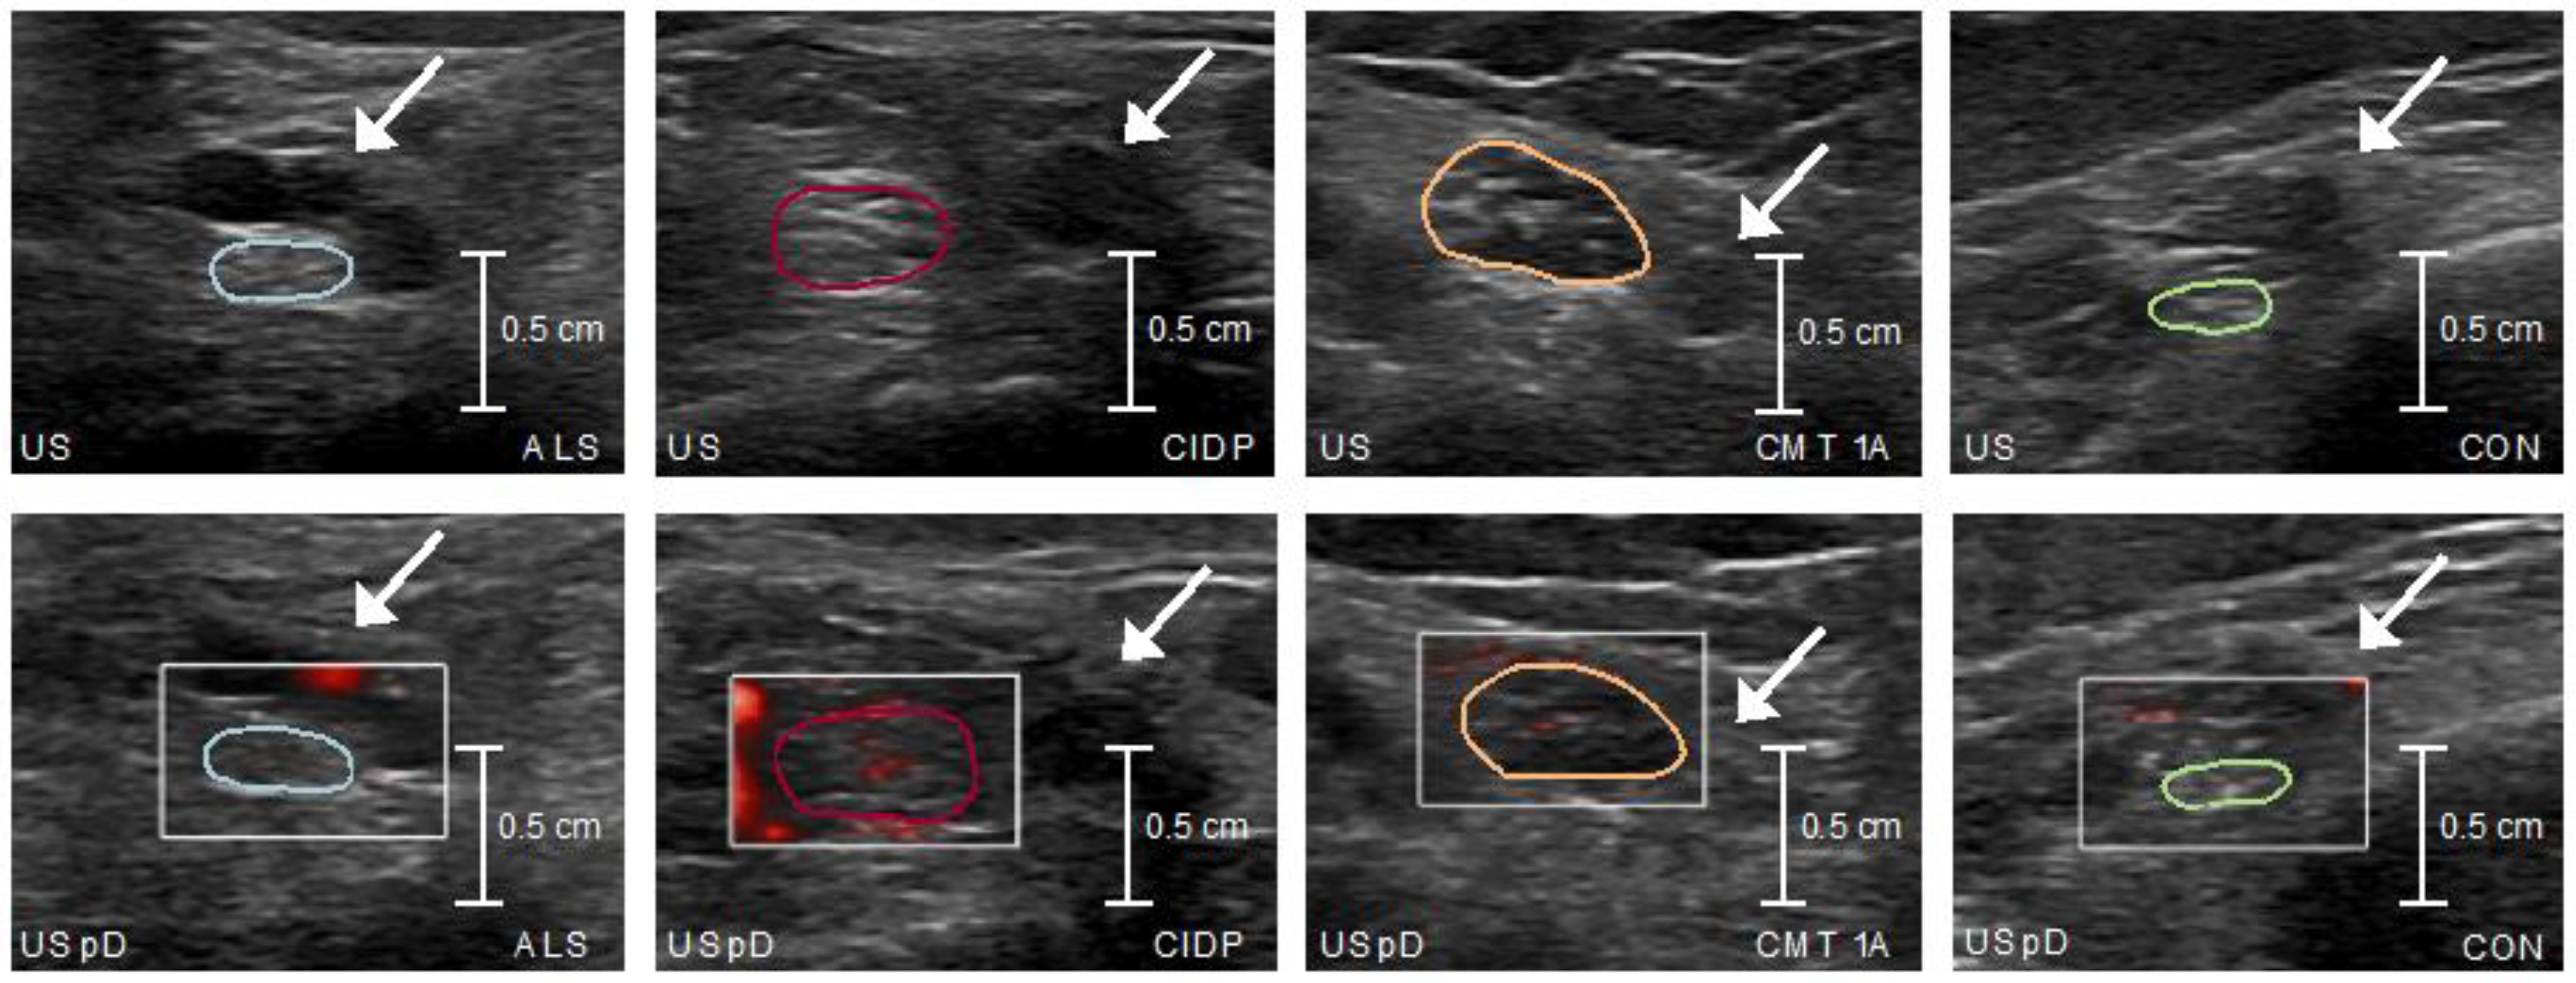

2.6.1. High-Resolution Nerve Ultrasound

2.6.2. Analysis of the Image Material